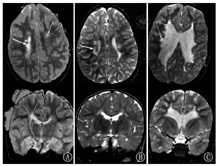

1 头颅MRI评估的发展历史早在1983年,Johnson等[3]首次报道了头颅MRI应用于新生儿脑发育及损伤的评估,展示了从胎龄36周至出生后20月龄不同时期髓鞘化的水平(图1);同时提供了早产儿脑室旁出血和后期白质软化、侧脑室扩张等病变(图2)。

髓鞘化进程 A:纠正胎龄36周;B:纠正胎龄42周;C:纠正胎龄52周;D:10月龄时;E:20月龄时

Myelination process A:36 weeks postmenstrual age;B:42 weeks postmenstrual age;C:52 weeks postmenstrual age;D:full term infant at 10 months;E:full term infant at 20 months